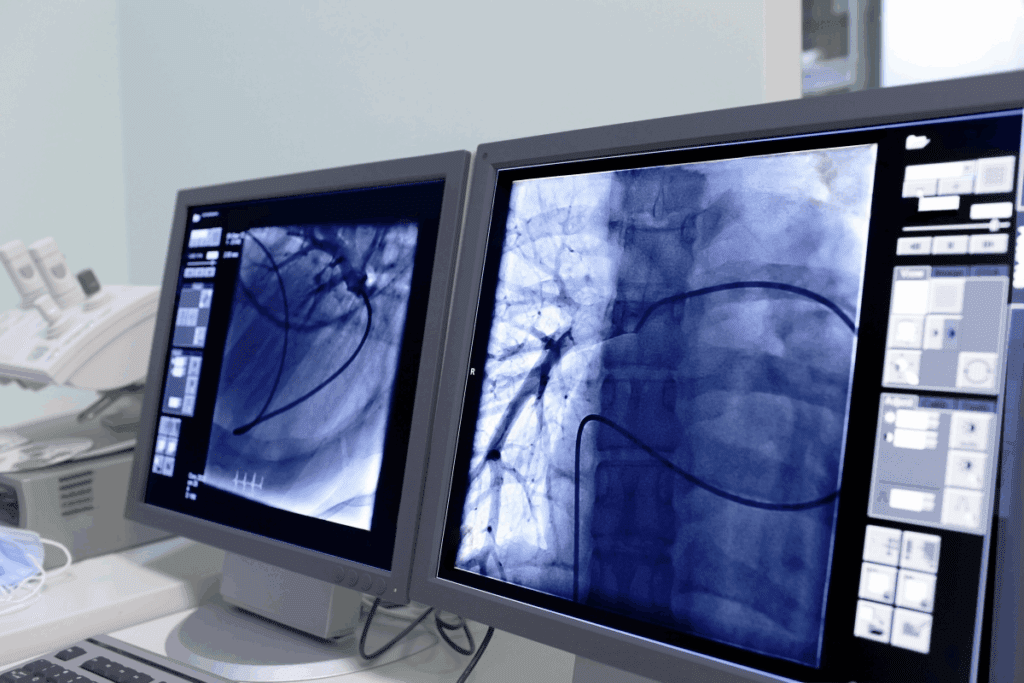

Fluoroscopy offers real-time X-ray images. It’s used in vascular interventions like angioplasty. It helps doctors see moving body structures.

Vascular interventions are a big part of IR, focusing on blood vessel diseases. Angioplasty and stenting are two main treatments. Angioplasty uses a balloon to widen narrowed arteries. Stenting places a metal tube to keep arteries open.